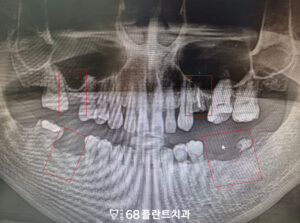

파노라마 사진을 통해 진단해 보니,

왼쪽 위 치아는 머리 부분이

완전히 부러져 저작 기능을

전혀 할 수 없는 상태였습니다.

다른 부위도 치아가

상실되어 있었습니다.

하지만 환자분의 경우

상악동과 치조골 사이의

거리가 매우 가까워

임플란트를 지탱할 만한

뼈의 높이가 부족했습니다.